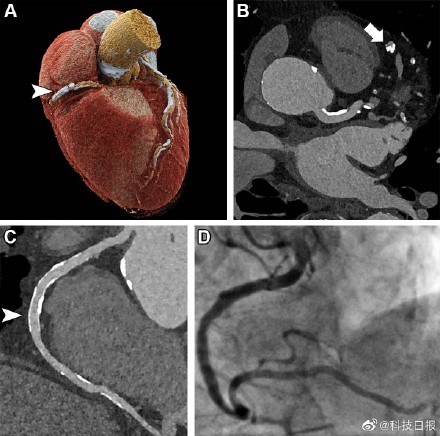

据发表在北美放射学会杂志《放射学》上的一项研究,德国弗莱堡大学研究团队开发出的超高分辨率CT技术能实现出色的图像质量,为冠状动脉疾病高危患者提供准确诊断。超高分辨率冠状动脉CT血管造影(UHR-CCTA)是一种有前景的评估冠心病高危患者的无创性工具,它使用的是研究团队新引进的光子计数CT扫描仪,对冠状动脉病变的诊断具有较高的敏感性和特异性。(科技日报记者 张佳欣,图片来源:北美放射学会)